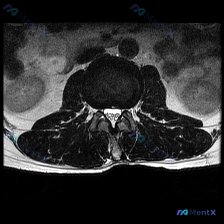

分享一张颈椎MRI T2轴位片,整理了完整的读片和分析思路,大家一起讨论看看。 病例基本影像信息 这是一张颈椎椎间盘水平的T2加权轴位图像,图像对比度良好,脑脊液呈高信号,脊髓中等信号,椎间盘中低信号,没有明显严重伪影,解剖层次清晰。 系统观察各个结构: 1. 骨骼关节:椎体形态完整,椎体后缘可见轻...

刚整理了一份很有启发的颈椎MRI读片病例,核心问题是“这张图里能观察到椎间盘病变吗?”,把完整分析思路分享给大家。 影像基本信息 这是一张颈椎MRI轴位T2加权图像,我们先把观察到的结构特征理清楚: 1. 椎体与椎管:脑脊液呈高信号,脊髓居中,形态规整,内部没有明显异常信号(无水肿灶);椎体后缘有轻...

整理了这张颈椎MRI读片病例和完整分析思路,分享给大家一起讨论 病例与影像基础信息 本次读片对象为颈椎MRI-T2序列轴位单张影像,核心问题是观察图像是否存在椎间盘病变: 1. 影像质量良好,对比度清晰,脊髓、脑脊液、软组织结构显示清楚,无明显运动伪影,扫描层面为颈椎中下段水平 2. 核心影像表现:...

刚看到一个有意思的读片病例,用户提供了一张颈椎MRI-T2序列轴位图像,明确提问是围绕「椎间盘病变」的观察,整理一下完整分析思路分享给大家。 一、影像基本信息 这是颈椎中下段的MRI-T2加权轴位图像,我们先按层次梳理客观观察结果: 1. 椎管与脊髓:脊髓位于椎管中央,形态规则,内部信号没有异常高/...